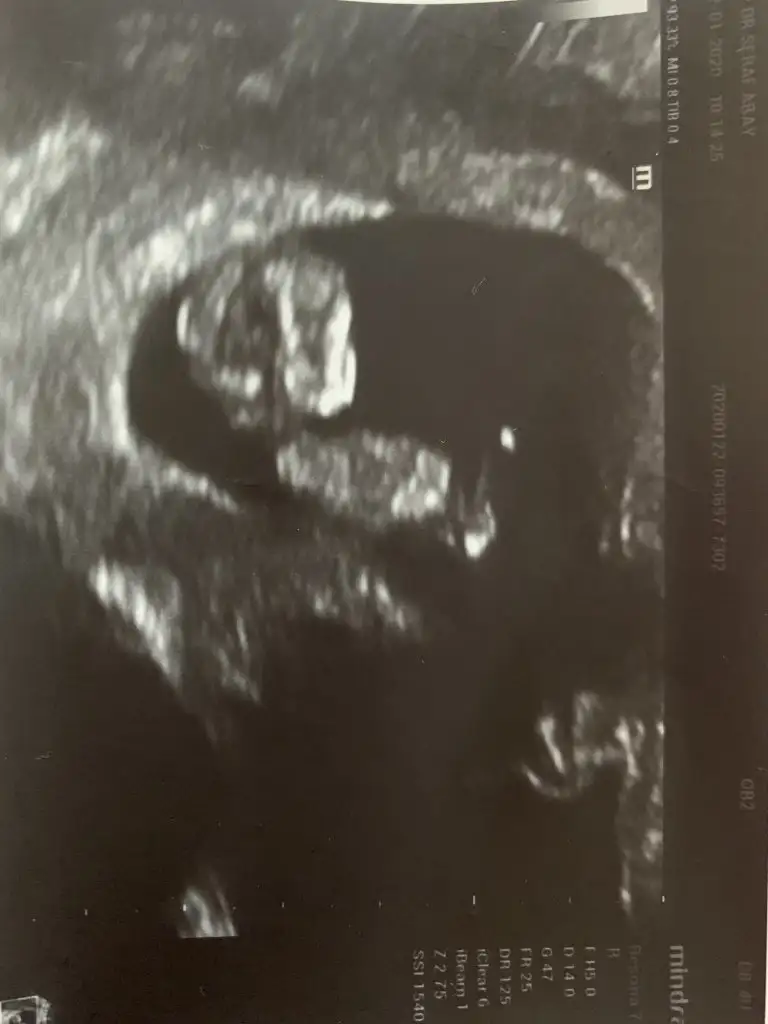

Eklentiler

• IMG-20200123-WA0008.webp

IMG-20200123-WA0008.webp

22 KB · Görüntüleme: 47